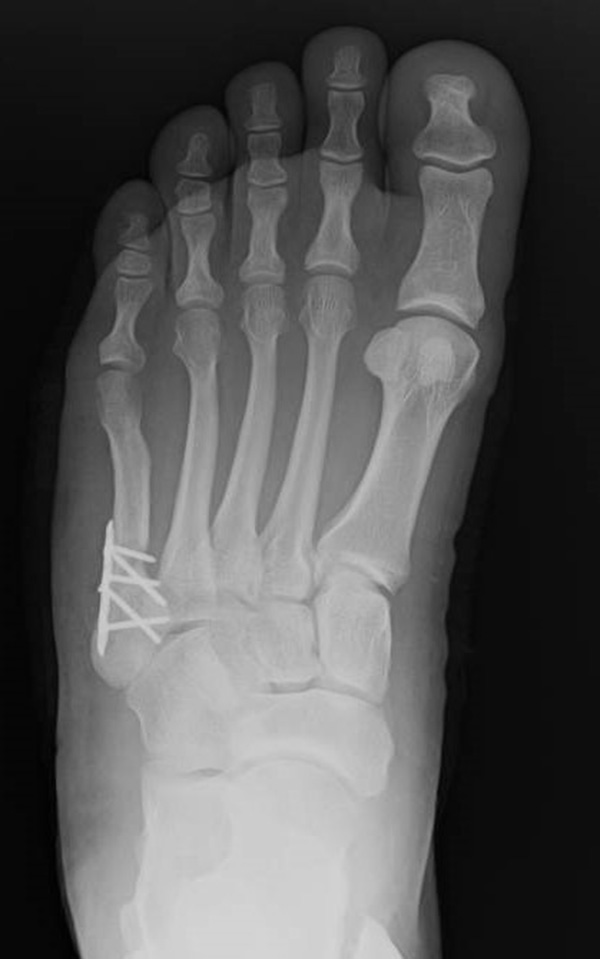

Abb. 3a, b: Präoperatives (a) und postoperatives (b) Röntgenbild bei Korrektur einer Typ I Deformität durch eine Exostosenabtragung.